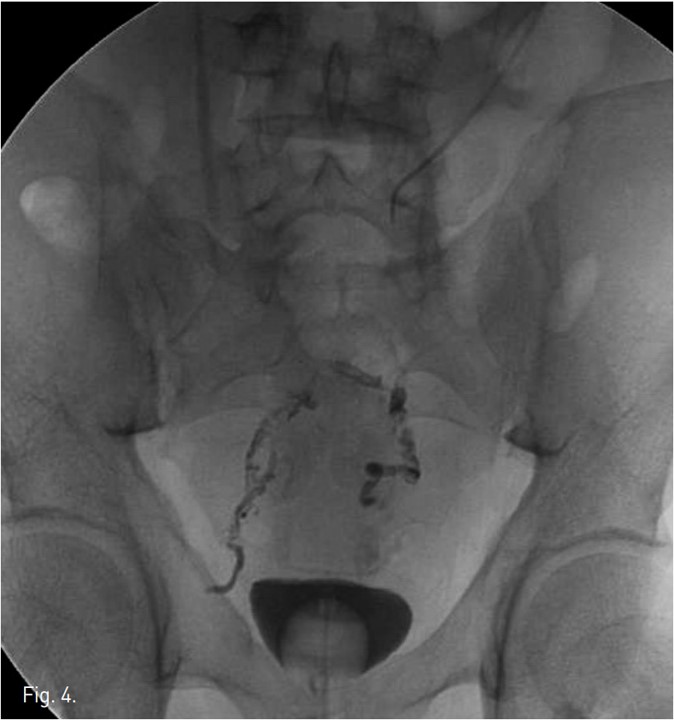

투시하에 간문맥 말초부위를 경피적으로 천자하여 5Fr sheath를 삽입하였다. 5Fr Davis catheter를 SMV에 위치시키고 시행한 portogram 상, IMV가 확장 되어 있고 rectum으로 hepatofugal blood flow를 보이며 rectum에서 varices를 형성한 후 (Fig. 2~3) internal iliac vein 으로 drain 되고 있음.

Fig. 2.

Fig. 2 & 3. Transhepatic portogram demonstrates dilated IMV and hepatofugal flow (Fig. 2) with development of rectal varices (Fig. 3).